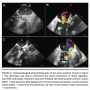

With respect to the mechanism of occurrence of significant MR, angiography was not able to determine the mechanism in any of the cases (Figure 1), while TEE ascertained the mechanism in 100% of cases. One case (9% of the total cases of MR) developed grade IIB significant MR due to mechanical asynchrony because of the appearance of a new left branch block, which was transitory. Three cases (27%) were due to an “impingement” of the prosthesis on the anterior leaflet of the

mitral valve because of low implantation of the prosthesis. The problem was resolved by repositioning the device in the direction of the ascending aorta prior to definitive release. In 2 cases (18%), the mechanism was the appearance of an anterior systolic movement of the mitral valve with the dynamic obstruction of the left ventricle outflow tract and moderate-severe MR immediately after the valvuloplasty (Figure 2), which resolved after the administration of intravenous beta-blockers. In 1 case (9%), after balloon valvuloplasty and prior to prosthesis implantation, a laceration of the anterior commissure of the mitral valve resulted in grade III MR (Figure 2). After implantation of the aortic percutaneous prosthesis and subsequent improvement of the hemodynamic conditions, the degree of MR was reduced at the end of the procedure to grade III. In 4 cases (36%), the mechanism was attributed to a functional cause, ie, the transitory alteration of the left ventricular function during the release of the device, which continued to diminish progressively during the succeeding minutes.